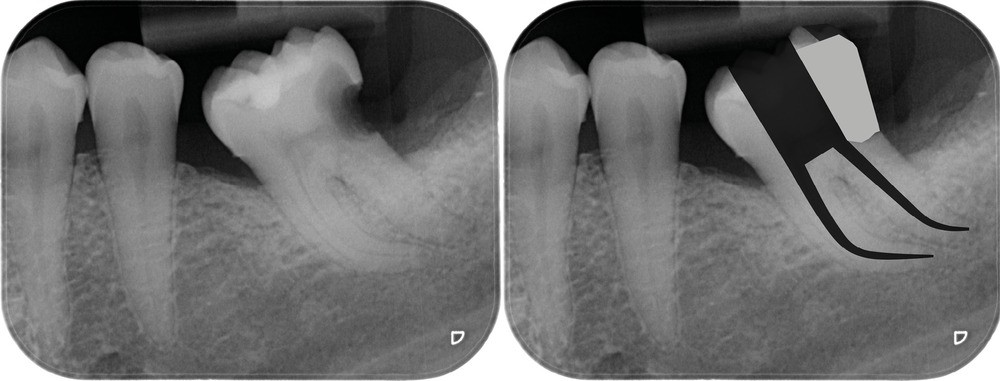

Une cavité d’accès trop large optimiserait le pronostic endodontique mais compromettrait le pronostic biomécanique. C’est le cas de la cavité d’accès traditionnelle, qui a longtemps été « au service » du praticien réalisant le traitement canalaire (dentist-centered dentistry ou dentisterie centrée sur le praticien). Les étapes d’instrumentation, d’irrigation et d’obturation étaient ainsi facilitées grâce à des accès visuel et instrumental exagérés, aux dépens de structures dentaires saines (fig. 4).

Une cavité d’accès moderne, dictée par l’anatomie et la pathologie de la dent, optimiserait à la fois les pronostics endodontiques et biomécaniques et donc la longévité de la dent sur l’arcade (patient-centered dentistry ou dentisterie centrée sur le patient) (fig. 5).